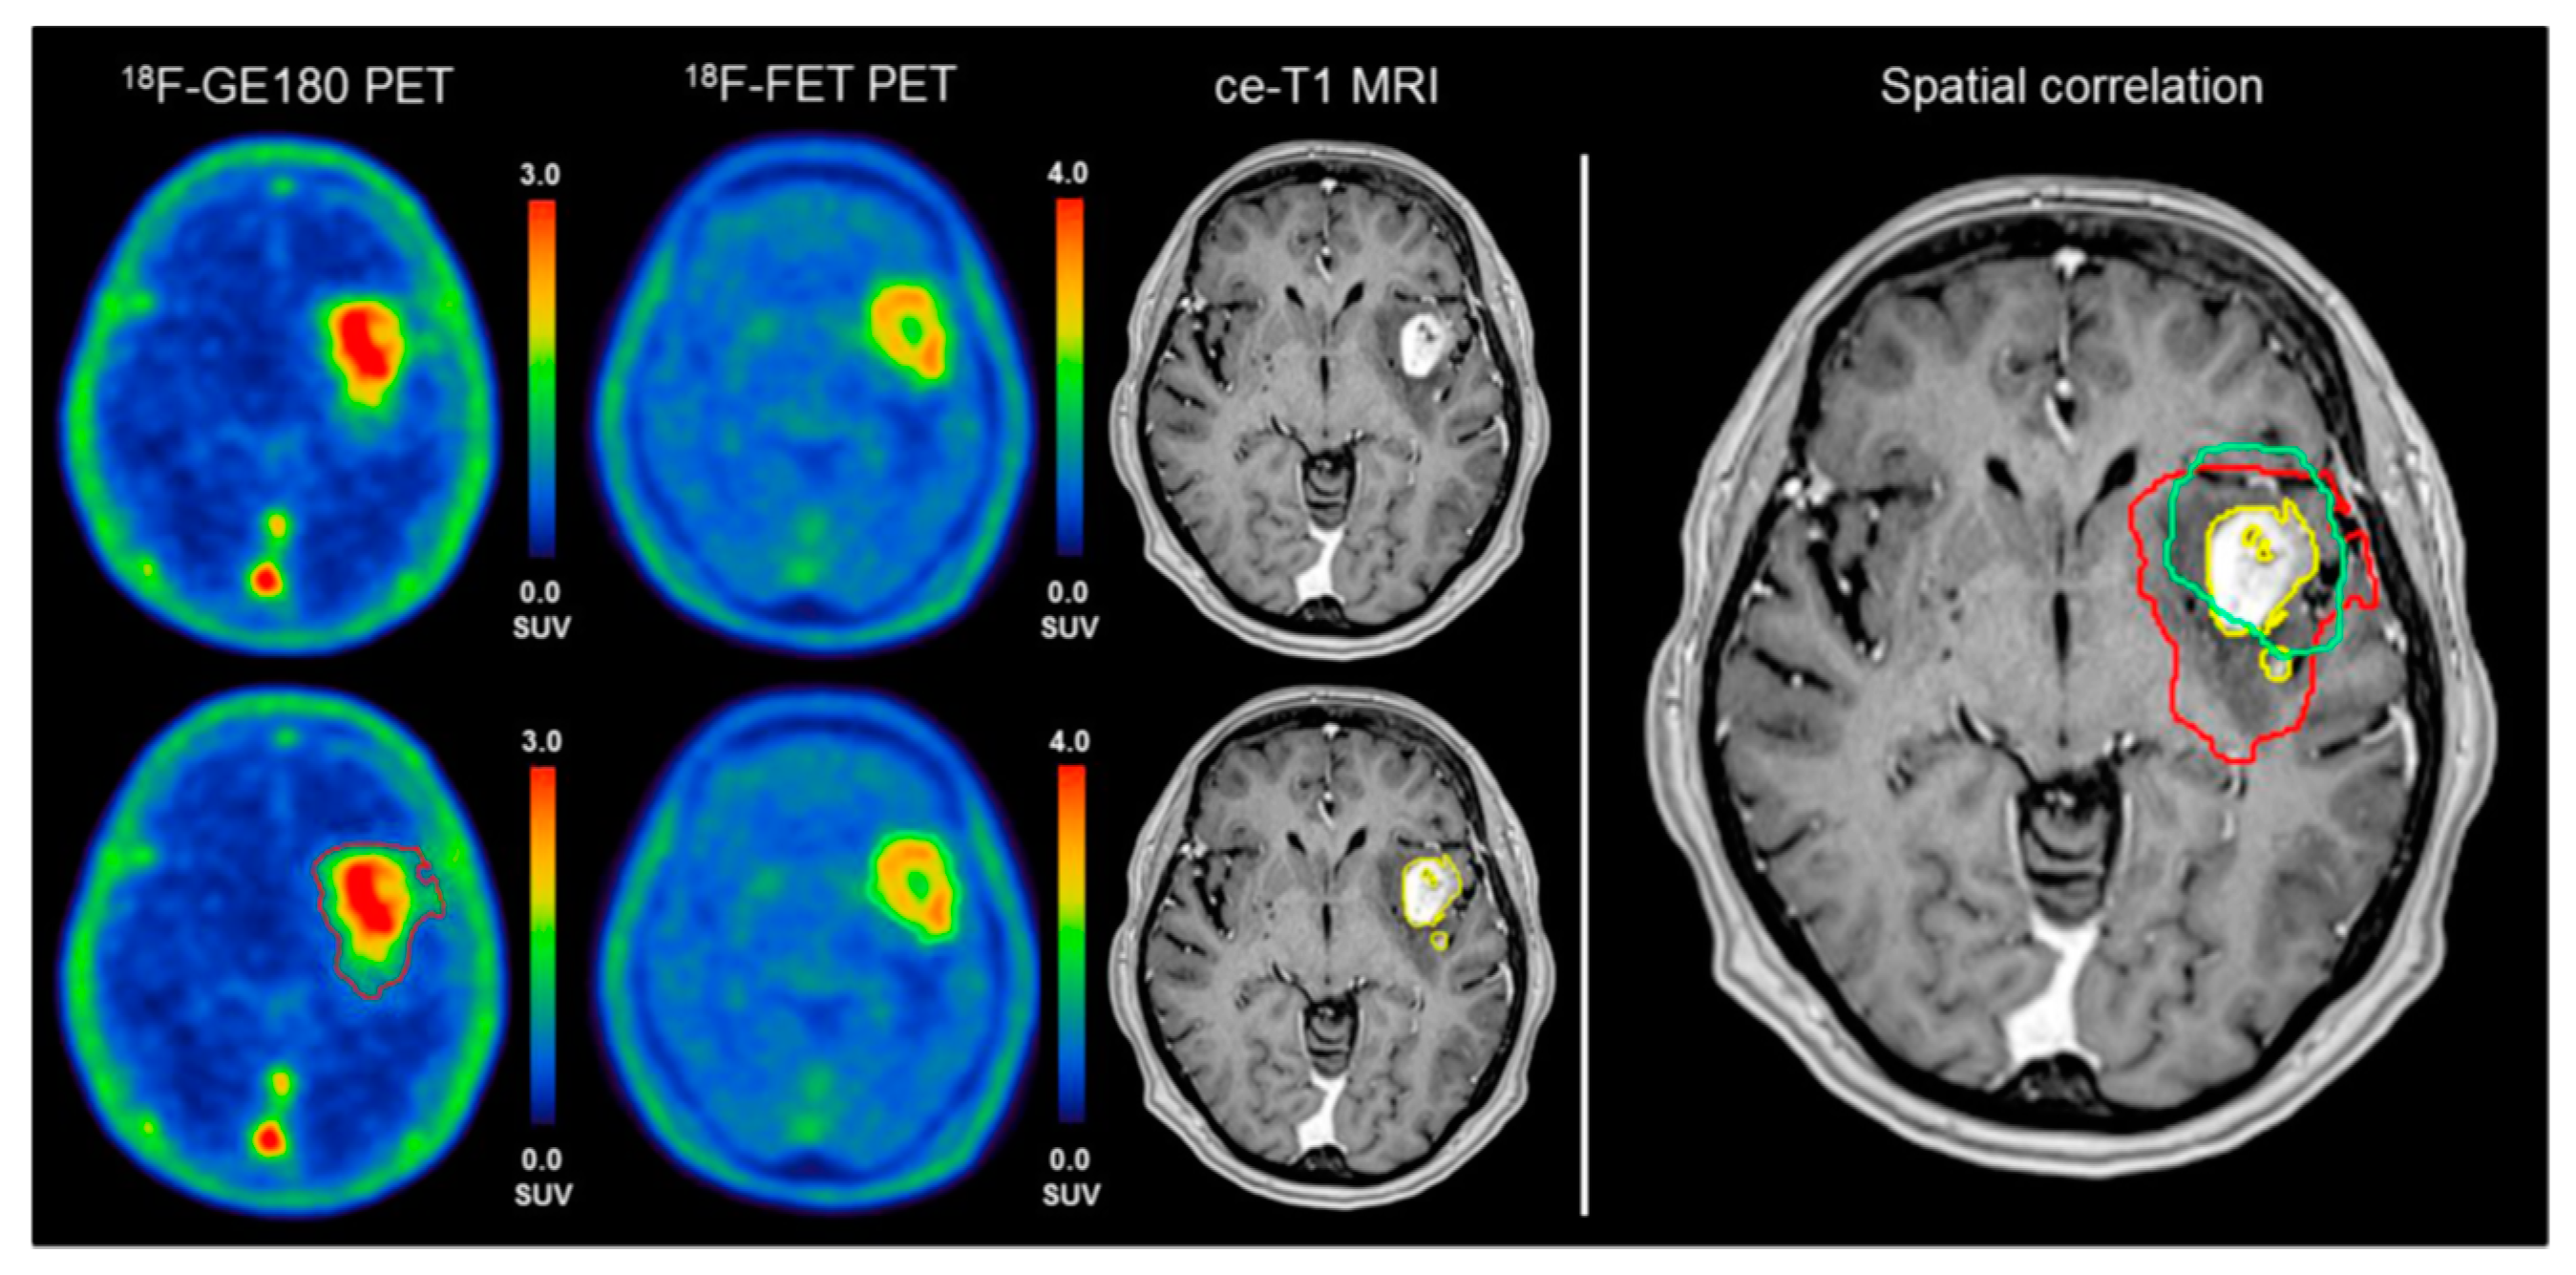

- Davis, K.A.; Nanga, R.P.; Das, S.; Chen, S.H.; Hadar, P.N.; Pollard, J.R.; Lucas, T.H.; Shinohara, R.T.; Litt, B.; Hariharan, H.; et al. Glutamate imaging (GluCEST) lateralizes epileptic foci in nonlesional temporal lobe epilepsy. Sci. Transl. Med. 2015, 7, 309ra161. [Google Scholar] [CrossRef] [PubMed]

- Neal, A.; Moffat, B.A.; Stein, J.M.; Nanga, R.P.R.; Desmond, P.; Shinohara, R.T.; Hariharan, H.; Glarin, R.; Drummond, K.; Morokoff, A.; et al. Glutamate weighted imaging contrast in gliomas with 7 Tesla magnetic resonance imaging. Neuroimage Clin. 2019, 22, 101694. [Google Scholar] [CrossRef] [PubMed]